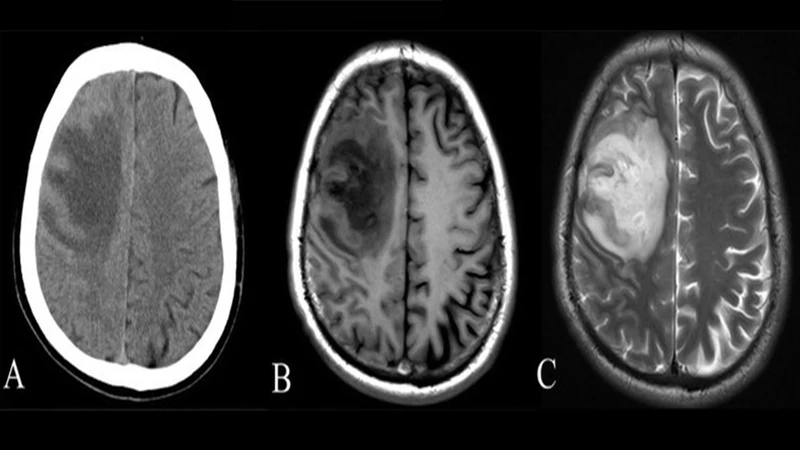

CT excels at imaging bone, blood, and lung tissue. It is fantastic for identifying dense structures. Its ability to quickly detect acute bleeds and complex fractures makes it the workhorse of the emergency room.

MRI excels at imaging soft tissues. It provides unparalleled detail of the brain, spinal cord, ligaments, tendons, and muscles. This makes it the superior choice for diagnosing conditions like ligament tears, tumors in soft tissue, and neurological diseases.